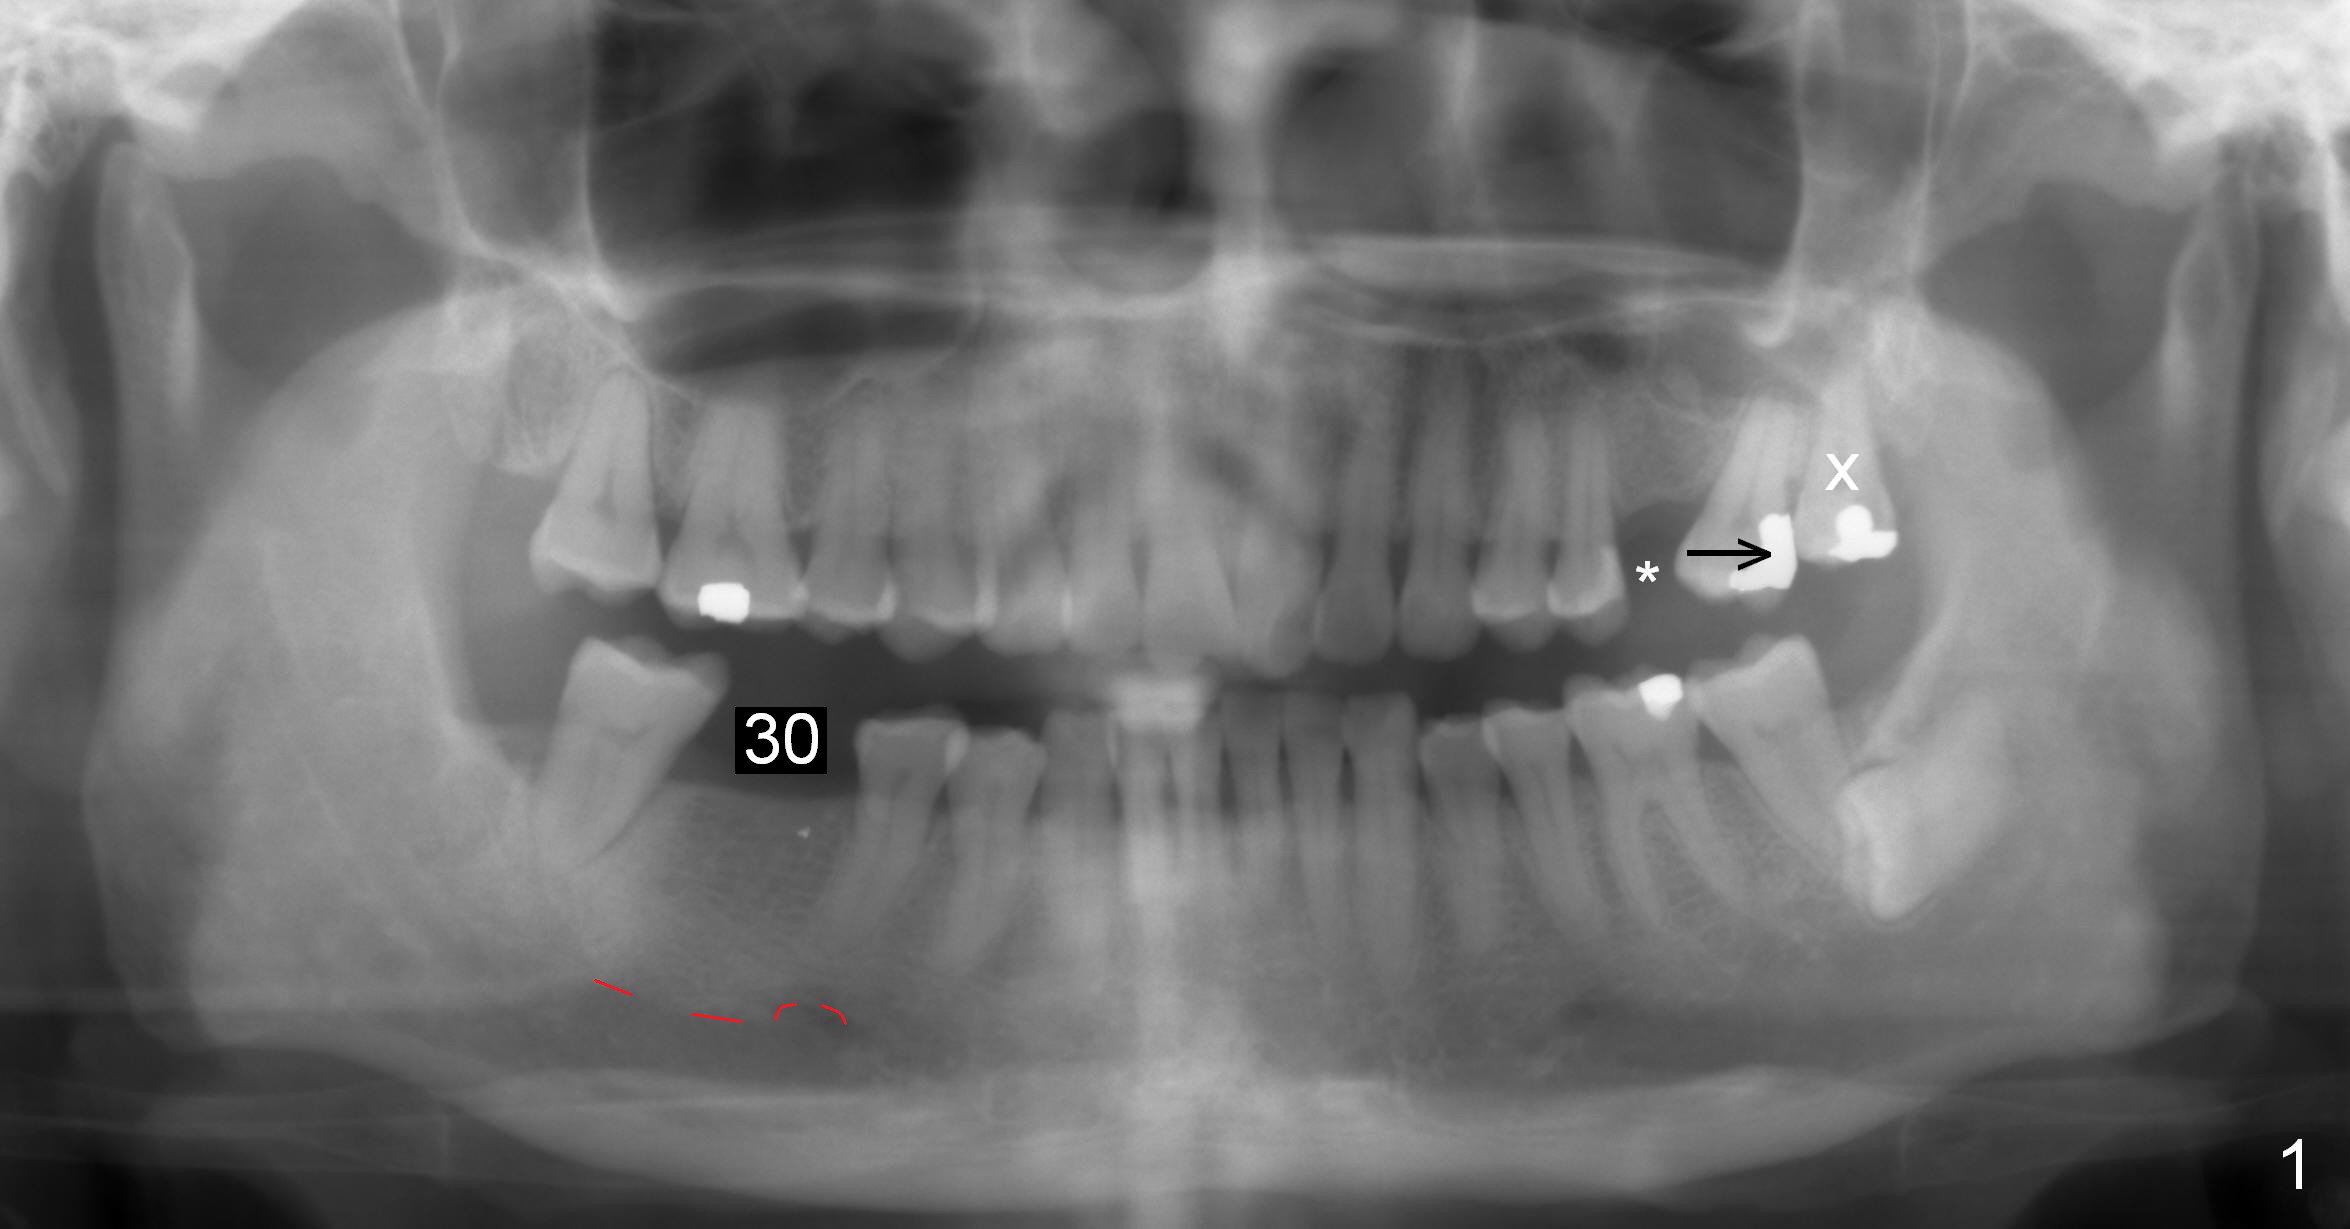

When the tooth #15 is distalized (Fig.3), place an implant at #14 (Fig.4 green), parallel to the tooth #13 and extract #16 (black). When the implant osteointegrates, place an abutment (Fig.5 pink), provisional (white) and bracket at #14. The implant is used as an anchorage to further distalize #15 until the latter reaches the normal position (Fig.6). CT study shows how much the tooth movement is needed prior to implantation.